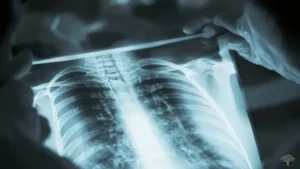

وكانت اللحظة الأكثر دراماتيكية وإنسانية في هذه القصة هي عندما طلب من زوجته، آنا بيرثا، أن تضع يدها في مسار الشعاع لمدة 15 دقيقة، مع لوح فوتوغرافي تحتها. عندما قام بتحميض الصورة، ظهرت صورة أيقونية: عظام يد زوجته واضحة تمامًا، مع خاتم زواجها الذي يظهر ككتلة داكنة تطفو حول عظمة الإصبع. يُقال إن آنا صرخت “لقد رأيت موتي!” عند رؤية الصورة. لقد كانت هذه أول “رونتجنوغرام” (صورة أشعة) بشرية في تاريخ الأشعة، ودليل قاطع على قوة هذا الاكتشاف.

| الطب | تحول التشخيص الطبي بشكل جذري. أصبح الأطباء قادرين لأول مرة على رؤية الكسور، وتحديد أماكن الرصاص والشظايا في أجساد الجنود، وتشخيص الأمراض الرئوية دون الحاجة إلى جراحة. |

مع مرور الوقت، بدأ المجتمع العلمي والطبي في فهم المخاطر ووضع بروتوكولات صارمة للسلامة. اليوم، أصبحت إجراءات التصوير بالأشعة السينية آمنة للغاية. حيث يتم استخدام أقل جرعة ممكنة من الإشعاع لتحقيق الصورة المطلوبة، مع استخدام دروع الرصاص لحماية أجزاء الجسم الأخرى.